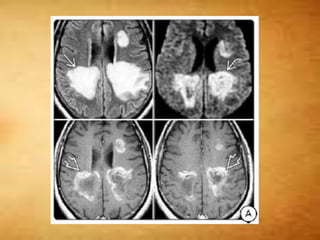

T1 C+

 Active demyelination - transient enhancement

- Punctate, nodular, linear, and rim patterns are

seen

 Large tumefactive lesions – horseshoe

enhancement- open nonenhancing segment

facing the cortex

 Cortical demyelination - Leptomeningeal

enhancement

 Steroid administration significantly reduces

lesion enhancement

T1 C+  Activedemyelination - transient enhancement - Punctate, nodular, linear, and rim patterns are seen  Large tumefactive lesions – horseshoe enhancement- open nonenhancing segment facing the cortex  Cortical demyelination - Leptomeningeal enhancement  Steroid administration significantly reduces lesion enhancement